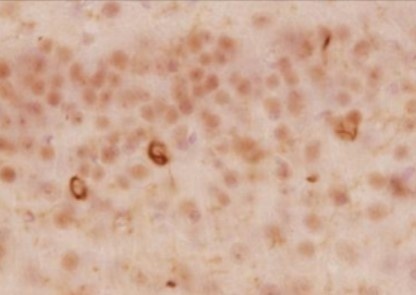

Immunohistochemistry

Species: Human (Dementia with Lewy bodies)

Site: Brain

Data by courtesy of

Dr. Iwatsubo, Graduate School of Medicine, The University of Tokyo